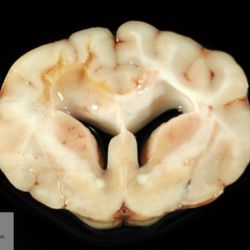

Pàgina anterior de 637 Pàgina següent 3181 total Bovine Specie: Bovine Organ: Bone Lesion: Scoliosis Lesion modifier: - Disease: Schmallenberg Files/Expedient: N-55/13 Position: 253 (1 views) Bovine Specie: Bovine Organ: Fetus Lesion: Scoliosis Lesion modifier: - Disease: Schmallenberg Files/Expedient: N-55/13 Position: 253 (1 views) Bovine Specie: Bovine Organ: Joint Lesion: Arthrogryposis Lesion modifier: - Disease: Schmallenberg Files/Expedient: N-55/13 Not viewed Canine Specie: Canine Organ: Brain Lesion: Malacia Lesion modifier: - Disease: - Files/Expedient: N-570/09 Not viewed Canine Specie: Canine Organ: Brain Lesion: Malacia Lesion modifier: - Disease: - Files/Expedient: N-570/09 Position: 253 (1 views) Pàgina anterior de 637 Pàgina següent Títol Select...Avian (Exotic) (110)Avian (Poultry) (76)Bovine (317)Canine (935)Caprine (47)Equine (257)Feline (326)Ferret (19)General (127)Marine mammal (22)Non-human primate (20)Ovine (328)Porcine (379)Rabbit (61)Reptile (38)Rodent (28)Wildlife (91) Format Select...- (60)Abomasum (37)Adrenal gland (10)Blood (7)Blood vessel (50)Body as a whole (19)Bone (57)Bone marrow (21)Brain (93)Cloaca (1)Diaphragm (2)Ear (5)Esophagus (39)Eye (16)Fetus (12)Gallbladder (23)Gizzard (2)Heart (265)Intestine (356)Joint (32)Kidney (443)Larynx (5)Liver (326)Lung (264)Lymph node (91)Mammary gland (10)Mediastinum (1)Muscle (22)Nasal cavity (22)Nerve (7)Omasum (5)Oral cavity (63)Ovary (14)Oviduct (8)Pancreas (7)Parathyroid (5)Penis (10)Peritoneum (65)Pharynx (9)Pituitary gland (6)Placenta (7)Prostate (8)Proventriculus (3)Reticulum (1)Rumen (28)Sinus (7)Skin (181)Spinal cord (15)Spleen (105)Stomach (125)Teeth (1)Testicle (11)Thoracic cavity (31)Thymus (13)Thyroid gland (5)Tongue (32)Tonsils (11)Trachea (11)Urethra (5)Urinay bladder (61)Uterus (27)Vagina (1)Vulva (1)Yolk sac (1) Cobertura Select...- (152)Abomasitis (26)Abscess (27)Acidosis (1)Adenocarcinoma (20)Adenoma (9)Aerosacculitis (6)Agenesis (1)Agnathia (1)Alopecia (7)Amyloidosis (12)Aneurysm (6)Angiectasis (1)Anthracosis (1)Arteritis (11)Arthritis (15)Arthrogryposis (6)Artifact (4)Ascites (13)Atelectasis (8)Atherosclerosis (5)Atresia (1)Atrial septal defect (2)Atrophy (10)Autolysis (7)Bronchitis (6)Bronchopneumonia (26)Cachexia (2)Carcinoma (103)Cardiomyopathy (19)Cellulitis (2)Chemodectoma (4)Cholangiohepatitis (4)Cholangitis (19)Cholecystitis (4)Cholestasis (5)Chondrodysplasia (2)Chondrosarcoma (2)Chronic passive congestion (13)Chylothorax (2)Cirrhosis (6)Coelomitis (3)Coenurus cerebralis (4)Colitis (40)Congestion (17)Conjunctivitis (5)Coronitis (3)Cryptorchidism (3)Cyst (25)Cystitis (24)Dermatitis (69)Diaphragmatic hernia (4)Dilation (28)Discospondylitis (1)Disseminated intravascular coagulation (7)Dyschondroplasia (1)Dysplasia (29)Ectopia cordis (1)Ectopic ureter (1)Edema (55)Emphysema (5)Encephalitis (5)Endocardiosis (14)Endocarditis (26)Endometritis (5)Enteritis (118)Enterolith (6)Epulis (3)Esophagitis (14)Fasciitis (1)Fibrosis (7)Fibrous osteodystrophy (8)Fistula (1)Folliculitis (3)Fracture (2)Gastritis (34)Gingivitis (5)Glioma (8)Glomerulonephritis (21)Glossitis (25)Glycogenosis (1)Gout (8)Granuloma (2)Granulosa cell tumor (4)Hemangioma (9)Hemangiosarcoma (46)Hematoma (8)Hemoglobinuria (2)Hemopericardium (12)Hemoperitoneum (2)Hemorrhage (100)Hemosiderosis (7)Hemothorax (2)Hepatitis (78)Hernia (11)Histiocytosis (3)Hydatid cyst (11)Hydrocephalus (9)Hydrometra (1)Hydronephrosis (22)Hydropericardium (6)Hydrothorax (3)Hydroureter (5)Hyperkeratosis (8)Hyperostosis (4)Hyperplasia (37)Hypertrophy (9)Hypopigmentation (1)Hypoplasia (7)Hypopyon (1)Impaction (6)Infarction (63)Insulinoma (6)Intussusception (5)Jaundice (17)Laminitis (2)Laryngitis (2)Leiomyoma (5)Leukemia (13)Lipidosis (36)Lipoma (7)Lymphadenitis (45)Lymphadenopathy (7)Lymphangiectasia (6)Lymphangitis (5)Lymphoma (221)Malacia (11)Malignant melanoma (15)Mast cell tumor (11)Mastitis (8)Megaesophagus (2)Melanosis (3)Melena (4)Meningioma (6)Meningitis (6)Meningocele (2)Meningoencephalitis (5)Mesothelioma (5)Methemoglobinemia (2)Mineralization (10)Mucocele (5)Mucometra (1)Multilobular bone tumor (1)Mummification (3)Myelofibrosis (1)Myocarditis (4)Myositis (5)Necrosis (81)Nephritis (113)Nephroblastoma (6)Nephrosclerosis (1)Nephrosis (14)Neuritis (1)Obstruction (13)Omasitis (4)Omphalitis (1)Omphalophlebitis (7)Orchitis (4)Osteoarthrosis (5)Osteomyelitis (9)Otitis (2)Palatoschisis (3)Pancreatitis (3)Panniculitis (3)Papilloma (7)Parakeratosis (14)Patent ductus arteriosus (6)Peliosis hepatis (1)Perforation (17)Pericarditis (35)Peritonitis (39)Persistent right aortic arch (1)Pharyngitis (2)Pheochromocytoma (2)Phlebitis (2)Placentitis (6)Pleuritis (21)Pleuropneumonia (24)Pneumonia (109)Pneumothorax (3)Polycystosis (14)Polyp (5)Polyserositis (6)Posthitis (1)Proctitis (4)Prolapse (3)Prostatitis (3)Proventriculitis (1)Pyelonephritis (24)Pyometra (6)Pyothorax (4)Rhinitis (11)Rumenitis (6)Rupture (24)Salpingitis (3)Sarcoma (57)Sclerosis (1)Scoliosis (2)Seminoma (2)Sequestrum (2)Serous atrophy (14)Sinusitis (7)Splenitis (14)Splenomegaly (9)Spondylitis (6)Spondylosis (1)Stenosis (9)Stomatitis (32)Tenosynovitis (2)Teratoma (3)Thricobezoar (2)Thrombosis (16)Tonsilitis (4)Torsion (13)Tracheitis (4)Tympany (7)Typhlitis (8)Typhlocolitis (4)Ulcer (43)Urethritis (1)Urolithiasis (36)Uroperitoneum (1)Uveitis (1)Vasculitis (15)Ventricular septal defect (3)Volvulus (11) Matèria Select... - (14)- (1653)- (152)Abomasitis - Catarrhal (2)Abomasitis - Catarrhal-hemorrhagic (1)Abomasitis - Chronic (1)Abomasitis - Fibrinous-necrotizing (2)Abomasitis - Hyperplasic (5)Abomasitis - Hyperplasic - Chronic (1)Abomasitis - Necrotic (1)Abomasitis - Necrotizing (2)Abomasitis - Ulcerative (5)Adenocarcinoma (9)Aerosacculitis - Granulomatous (1)Amyloidosis - Chronic (1)Arteritis - Necrotic (2)Arteritis - Necrotizing (1)Arthritis - Chronic (4)Arthritis - Fibrinous-purulent (3)Arthritis - Serous (4)Arthritis - Subacute (1)Ascites - Serous (1)Atrophy - Serous (1)Bronchitis - Catarrhal (3)Bronchitis - Suppurative (1)Bronchopneumonia - Catarrhal-purulent (17)Bronchopneumonia - Fibrinous (1)Bronchopneumonia - Granulomatous (1)Bronchopneumonia - Purulent (1)Bronchopneumonia - Suppurative (5)Carcinoma - Adenocarcinoma (33)Carcinoma - Adenocarcinoma - Hepatocellular (2)Carcinoma - Adenocarcinoma - Mucinous (1)Carcinoma - Basosquamous (1)Carcinoma - Cholangiocellular (3)Carcinoma - Hepatocellular (4)Carcinoma - Metastatic (3)Carcinoma - Squamous cell carcinoma (13)Carcinoma - Transitional cell (2)Cardiomyopathy - Dilated (13)Cardiomyopathy - Hypertrophic (6)Cellulitis - Necrotizing (1)Cholangitis - Chronic (8)Cholangitis - Hyperplasic (3)Cholecystitis - Fibrinous-necrotizing (1)Coelomitis - Fibrinous (1)Coelomitis - Granulomatous (1)Colitis - Catarrhal (3)Colitis - Catarrhal-hemorrhagic (1)Colitis - Fibrinous (1)Colitis - Fibrinous-necrotizing (1)Colitis - Fibrinous-necrotizing (Diphtheritic) (6)Colitis - Granulomatous (2)Colitis - Hemorrhagic (4)Colitis - Hemorrhagic-necrotizing (3)Colitis - Necrotizing (2)Colitis - Ulcerative (6)Congestion - Chronic (2)Conjunctivitis - Hyperplasic (1)Conjunctivitis - Purulent (3)Coronitis - Ulcerative (1)Cystitis - Chronic (3)Cystitis - Fibrinous (1)Cystitis - Fibrinous-necrotizing (1)Cystitis - Follicular (1)Cystitis - Hemorrhagic (6)Cystitis - Hemorrhagic-ulcerative (1)Cystitis - Necrotizing (9)Cystitis - Perforated (1)Dermatitis - Granulomatous (14)Dermatitis - Hyperkeratotic (10)Dermatitis - Hyperplasic (proliferative) (1)Dermatitis - Hyperplastic (10)Dermatitis - Necrotizing (4)Dermatitis - Pustular (4)Dermatitis - Ulcerative (2)Dilation - Chronic (1)Discospondylitis - Necrotizing (1)Dysplasia - Follicular (5)Edema - Interstitial (6)Emphysema - Interstitial (1)Encephalitis - Granulomatous (1)Encephalitis - Nonsuppurative (1)Endocardiosis - Mitral (7)Endocardiosis - Mitral - Chronic (5)Endocarditis - Valvular (6)Endocarditis - Valvular - Mitral (7)Endocarditis - Valvular - Pulmonic (1)Endocarditis - Valvular - Subacute (1)Endocarditis - Valvular - Subaortic (5)Endocarditis - Valvular - Tricuspid (4)Endometritis - Purulent (3)Endometritis - Purulent-hemorrhagic (2)Enteritis - Catarrhal (23)Enteritis - Catarrhal - Acute (1)Enteritis - Catarrhal-hemorrhagic (5)Enteritis - Catarrhal-hemorrhagic - Acute (2)Enteritis - Fibrinous (16)Enteritis - Fibrinous - Acute (3)Enteritis - Fibrinous-necrotizing (7)Enteritis - Granulomatous (14)Enteritis - Granulomatous - Chronic (1)Enteritis - Granulomatous - Multifocal (1)Enteritis - Hemorrhagic (17)Enteritis - Hemorrhagic - Acute (1)Enteritis - Hemorrhagic-necrotizing (1)Enteritis - Hyperplasic (proliferative) (4)Enteritis - Necrotizing (4)Enteritis - Necrotizing - Acute (1)Enteritis - Necrotizing - Hemorrhagic (1)Enteritis - Necrotizing-ulcerative (2)Enteritis - Ulcerative (1)Enteritis - Ulcerative-hemorrhagic (1)Esophagitis - Erosive-ulcerative (6)Esophagitis - Necrotizing (4)Esophagitis - Ulcerative (1)Esophagitis - Ulcerative-necrotizing (1)Fasciitis - Fibrinous-purulent (1)Folliculitis - Purulent (2)Gastritis - Catarrhal (2)Gastritis - Chronic (1)Gastritis - Follicular (1)Gastritis - Hemorrhagic (2)Gastritis - Hemorrhagic-necrotizing (1)Gastritis - Hypertrophic (2)Gastritis - Inclusion bodies (1)Gastritis - Mineralization (1)Gastritis - Mycotic (1)Gastritis - Necrotizing (2)Gastritis - Ulcerative (6)Gastritis - Uremic (3)Gingivitis - Erosive (2)Gingivitis - Hyperplasic (proliferative) (1)Gingivitis - Necrotizing (1)Glomerulonephritis - Chronic (7)Glomerulonephritis - Membranoproliferative (3)Glomerulonephritis - Membranoproliferative - Chronic (1)Glomerulonephritis - Membranous (3)Glomerulonephritis - Membranous - Chronic (1)Glomerulonephritis - Proliferative (2)Glomerulonephritis - Subacute (1)Glossitis - Erosive (2)Glossitis - Granulomatous (6)Glossitis - Hyperplasic (1)Glossitis - Hyperplasic (proliferative) (2)Glossitis - Hyperplastic (1)Glossitis - Necrotizing (2)Glossitis - Necrotizing - Focal (1)Glossitis - Ulcerative (6)Glossitis - Ulcerative - Multifocal (1)Glossitis - Ulcerative - Subacute (1)Glycogenosis (1)Granuloma - Eosinophilic (1)Hemangiosarcoma - Metastatic (2)Hemorrhage - Acute (1)Hemorrhage - Subcapsular (3)Hepatitis - Abscess (9)Hepatitis - Acute (3)Hepatitis - Chronic (4)Hepatitis - Chronic interstitial (6)Hepatitis - Granulomatous (7)Hepatitis - Interstitial - Multifocal (1)Hepatitis - Interstitial - Subacute (1)Hepatitis - Necrotizing (17)Hepatitis - Necrotizing - Acute (2)Hepatitis - Necrotizing - Hemorrhagic (1)Hepatitis - Necrotizing - Subacute (1)Hepatitis - Pyogranulomatous (7)Hepatitis - Subacute (4)Hydronephrosis - Chronic (1)Hydropericardium - Chronic (1)Hyperplasia - Erythroid (1)Hyperplasia - Lymphoid (3)Hyperplasia - Myeloid (1)Hyperplasia - Nodular (8)Hypertrophy - Concentric (2)Hypertrophy - Eccentric (3)Infarction - Acute (17)Infarction - Acute - Multifocal (2)Infarction - Chronic (5)Infarction - Chronic - Multifocal (1)Infarction - Subacute (18)Infarction - Subacute - Focal (2)Laminitis - Chronic (2)Laryngitis - Necrotic (1)Laryngitis - Necrotizing (1)Leukemia - Lymphoid leukemia (2)Leukemia - Non-lymphoid leukemia (6)Lipidosis - Multifocal (1)Lipidosis - Panlobular (1)Lipidosis - Panlobular - Generalized (2)Lymphadenitis - Granulomatous (24)Lymphadenitis - Granulomatous - Chronic (3)Lymphadenitis - Hemorrhagic (1)Lymphadenitis - Necrotizing (5)Lymphadenitis - Necrotizing (caseous) (11)Lymphangitis - Granulomatous (1)Lymphangitis - Purulent (1)Lymphangitis - Ulcerative (1)Lymphoma - Alimentary lymphoma (7)Lymphoma - Cutaneous lymphoma (6)Lymphoma - Lymphosarcoma (2)Lymphoma - Mediastinal lymphoma (1)Lymphoma - Multicentric lymphoma (29)Malignant melanoma - Malignant (1)Malignant melanoma - Metastatic (1)Mast cell tumor - Metastatic (1)Mastitis - Fibrinous-purulent (2)Mastitis - Necrotic (1)Mastitis - Purulent (3)Mastitis - Suppurative (1)Meningitis - Fibrinous-purulent (2)Meningitis - Purulent (4)Meningoencephalitis - Necrotizing (3)Meningoencephalitis - Nonsuppurative (2)Mineralization - Metastatic (4)Myocarditis - Fibrous - Chronic (1)Myocarditis - Granulomatous (1)Myositis - Purulent (2)Necrosis - Acute (1)Necrosis - Cortical (5)Necrosis - Follicular (1)Necrosis - Papillary (8)Necrosis - Papillary - Acute (3)Necrosis - Subacute (3)Necrosis - Tubular (6)Nephritis - Embolic (2)Nephritis - Embolic suppurative (7)Nephritis - Granulomatous (27)Nephritis - Granulomatous - Chronic (1)Nephritis - Granulomatous - Multifocal (1)Nephritis - Interstitial (6)Nephritis - Interstitial - Acute (4)Nephritis - Interstitial - Chronic (41)Nephritis - Interstitial - Subacute (12)Nephritis - Purulent (7)Nephritis - Purulent - Acute (2)Nephritis - Purulent - Multifocal (3)Nephrosis - Cholemic (3)Nephrosis - Hemoglobinuric (10)Omasitis - Fibrinous-necrotizing (1)Omasitis - Hyperkeratotic (1)Omasitis - Necrotizing (2)Omphalophlebitis - Fibrinous-purulent (2)Omphalophlebitis - Purulent (3)Orchitis - Necrotizing (1)Osteomyelitis - Necrotizing (7)Osteomyelitis - Purulent (2)Otitis - Necrotizing (1)Otitis - Proliferative (1)Pancreatitis - Acute (1)Pancreatitis - Chronic (1)Pancreatitis - Granulomatous (1)Panniculitis - Fibrinous-purulent (1)Panniculitis - Necrotic (1)Panniculitis - Parasitic (1)Perforation - Acute (2)Pericarditis - Fibrinous (19)Pericarditis - Fibrinous - Subacute (1)Pericarditis - Fibrinous-necrotizing (1)Pericarditis - Fibrinous-purulent (3)Pericarditis - Fibrous (1)Pericarditis - Fibrous - Chronic (1)Pericarditis - Gangrenous (6)Pericarditis - Granulomatous (1)Pericarditis - Granulomatous - Chronic (2)Peritonitis - Acute (1)Peritonitis - Fibrinous (11)Peritonitis - Fibrinous - Subacute (1)Peritonitis - Fibrinous-purulent (5)Peritonitis - Fibrous (3)Peritonitis - Granulomatous (6)Peritonitis - Purulent (1)Peritonitis - Purulent-hemorrhagic (1)Peritonitis - Pyogranulomatous (3)Pharyngitis - Fibrinous-necrotizing (1)Pharyngitis - Ulcerative (1)Pheochromocytoma - Metastatic (1)Phlebitis - Purulent (1)Placentitis - Fibrinous-necrotizing (1)Placentitis - Necrotic (1)Placentitis - Necrotizing (1)Pleuritis - Chronic (1)Pleuritis - Fibrinous (3)Pleuritis - Fibrinous-purulent (2)Pleuritis - Fibrous (2)Pleuritis - Granulomatous (3)Pleuritis - Hyperplastic (2)Pleuritis - Purulent (2)Pleuritis - Pyogranulomatous (1)Pleuropneumonia - Fibrinous (13)Pleuropneumonia - Fibrinous-necrotizing (5)Pleuropneumonia - Granulomatous (2)Pleuropneumonia - Hemorrhagic-necrotizing (4)Pneumonia - Aspiration (11)Pneumonia - Bronchointerstitial (4)Pneumonia - Bronchointerstitial - Subacute (1)Pneumonia - Embolic (5)Pneumonia - Granulomatous (37)Pneumonia - Granulomatous - Multifocal (4)Pneumonia - Hemorrhagic-necrotizing (2)Pneumonia - Interstitial (7)Pneumonia - Interstitial - Acute (8)Pneumonia - Interstitial - Chronic (6)Pneumonia - Interstitial - Subacute (15)Pneumonia - Necrotizing (2)Pneumonia - Pyogranulomatous (2)Pneumonia - Verminous (5)Polyserositis - Fibrinous (6)Polyserositis - Fibrous (1)Proctitis - Fibrinous-necrotizing (1)Proctitis - Parasitic (2)Prostatitis - Purulent (1)Pyelonephritis - Acute (2)Pyelonephritis - Chronic (3)Rhinitis - Catarrhal (2)Rhinitis - Fibrinous (1)Rhinitis - Granulomatous (4)Rhinitis - Purulent (3)Rumenitis - Acute (1)Rumenitis - Erosive (1)Rumenitis - Necrotizing (1)Rupture - Acute (3)Sarcoma - Fibrosarcoma (12)Sarcoma - Hemangiosarcoma (11)Sarcoma - Histiocytic (7)Sarcoma - Metastatic (1)Sarcoma - Multilobular tumor of bone (1)Sequestrum - Chronic (2)Sinusitis - Suppurative (1)Splenitis - Granulomatous (8)Splenitis - Granulomatous - Chronic (1)Splenitis - Necrotizing (3)Splenitis - Necrotizing (caseous) (2)Spondylitis - Necrotizing (2)Stenosis - Intestinal (1)Stenosis - Valvular - Subaortic (4)Stomatitis - Erosive (12)Stomatitis - Erosive-ulcerative (3)Stomatitis - Fibrinous-necrotizing (1)Stomatitis - Fibrinous-necrotizing (Diphtheritic) (1)Stomatitis - Granulomatous (1)Stomatitis - Hyperplasic (1)Stomatitis - Hyperplasic (proliferative) (1)Stomatitis - Necrotizing (2)Stomatitis - Ulcerative (5)Stomatitis - Ulcerative - Multifocal (1)Stomatitis - Ulcerative-necrotizing (1)Tonsilitis - Necrotizing (4)Torsion - Acute passive hyperemia (5)Tracheitis - Catarrhal (3)Tracheitis - Fibrinous (1)Tracheitis - Granulomatous (1)Typhlitis - Catarrhal (1)Typhlitis - Fibrinous-necrotizing (2)Typhlitis - Hemorrhagic (2)Typhlitis - Ulcerative-hemorrhagic (1)Typhlocolitis - Fibrinous-necrotizing (2)Typhlocolitis - Proliferative (1)Ulcer - Chronic (6)Ulcer - Multifocal (2)Ulcer - Mycotic (1)Ulcer - Perforated (6)Urethritis - Hemorrhagic (1)Urolithiasis - Chronic (2)Uveitis - Granulomatous (1)Vasculitis - Granulomatous (1)Vasculitis - Necrotizing (1) Editor Select...- (1970)Acidosis (2)Actinobacillosis (Pleuropneumonia) (11)Aelurostrongylosis (2)African horse sickness (13)African swine fever (14)Alopecia X (1)Anaplasmosis (4)Anthrax (2)Aortic thromboembolism (feline) (7)Ascariasis (15)Aspergillosis (18)Atopic dermatitis (1)Atrophic rhinitis (3)Babesiosis (6)Blackhead (1)Bluetongue (11)Border disease (2)Bovine viral diarrhea (21)Brucellosis (2)Candidiasis (5)Canine distemper (14)Caprine arthritis-encephalitis (2)Capture myopathy (1)Cardiac insufficiency (17)Caseous lymphadenitis (7)Chlamydiosis (2)Classical swine fever (19)Clostridiosis (19)Coccidiosis (9)Coenurosis (4)Colibacillosis (21)Contagious ecthyma (7)Copper toxicosis (11)Cowdriosis (Heartwater) (3)Cryptococcosis (3)Cryptosporidiosis (2)Cysticercosis (23)Demodicosis (1)Diabetes (1)Dicrocoeliosis (5)Dictyocaulosis (4)Dirofilariasis (7)Discoid lupus erythematosus (3)Echinococcosis (17)Edema disease (7)Egg drop syndrome (1)Encephalitozoonosis (5)Enterotoxemia (1)Enzootic bovine leukosis (46)Epitheliogenesis imperfecta (3)Equine rhinopneumonitis (2)Equine verminous arteritis (strongylosis) (7)Erysipelas (5)Exudative epidermitis (7)Fasciolasis (11)Feline eosinophilic dermatoses (1)Feline hepatic lipidosis (8)Feline histiocytosis (4)Feline infectious peritonitis (38)Feline leukemia (4)Feline lower urinary tract disease (3)Feline panleukopenia (16)Feline viral rhinotracheitis (1)Flea allergy dermatitis (1)Foot and mouth disease (2)Gasterophilosis (4)Glasser's disease (15)Gousiekte (4)Gout (6)Haemonchosis (9)Hemolytic anemia (4)Hemorrhagic diathesis (1)Hepatic insufficiency (11)Hepatosis dietetica (7)Herpesvirosis (6)Hyperadrenocorticism (7)Hyperparathyroidism (10)Hypertrophic osteopathy (6)Hypervitaminosis D (1)Hypodermosis (1)Inclusion body hepatitis (4)Infectious bovine rhinotracheitis (5)Infectious bronchitis (5)Infectious canine hepatitis (13)Influenza (4)Juvenile nephropathy (8)Lamb dysentery (4)Leishmaniasis (28)Leptospirosis (1)Leukosis (5)Listeriosis (4)Lumpy skin disease (3)Maedi-visna (4)Malignant catarrhal fever (12)Mange (6)Mannheimiosis (5)Marek's disease (7)Metabolic bone disease (2)Mucoid enteropathy (5)Mulberry heart disease (5)Myasis (1)Mycobacteriosis (22)Mycosis fungoides (6)Myxomatosis (3)Necrobacillosis (5)Neonatal isoerythrolysis (6)Nocardiosis (4)Oestrosis (2)Onchocerciasis (1)Osteochondrosis (1)Ostertagiosis (6)Ovine pulmonary adenocarcinoma (5)Oxyuriasis (1)Pacheco's disease (4)Papillomatosis (6)Paratuberculosis (18)Parvovirosis (17)Pasteurellosis (11)Pemphigus foliaceus (1)Periodontal disease (1)Polioencephalomalacia of ruminants (4)Polyarteritis nodosa (3)Polycystic kidney disease (13)Porcine circovirosis (11)Porcine dermatitis and nephropathy syndrome (9)Porcine proliferative enteropathy (4)Porcine reproductive and respiratory syndrome (6)Porcine stress syndrome (1)Pox (13)Pregnancy toxemia (3)Proventricular dilatation disease (2)Pseudotuberculosis (yersiniosis) (2)Psittacine beak and feather disease (PBFD) (5)Pyoderma (4)Q fever (4)Rabbit hemorrhagic disease (2)Renal insufficiency (12)Reticuloendotheliosis (2)Rhodococcosis (1)Rickets (1)Rinderpest (2)Salmonellosis (34)Sarcosporidiosis (2)Schmallenberg (7)Septicemia (23)Spirocercosis (11)Streptococcosis (5)Strongylosis (1)Swine dysentery (5)Systemic coronavirosis (5)Tetralogy of Fallot (5)Theileriosis (13)Thromboembolism (5)Toxoplasmosis (11)Transmissible viral proventriculitis (1)Traumatic reticuloperitonitis (3)Traumatism (16)Tuberculosis (58)Ulcerative lymphangitis (1)Uremic syndrome (20)Viral arthritis (6)White muscle disease (9)Wobbler syndrome (2)Xanthomatosis (1)Zygomycosis (4) Idioma Select...- (1180)Bacterial (501)Degeneration (106)Fungal (46)Hemodynamic (112)Idiopathic (22)Inflammation (58)Malformation (88)Neoplasia (343)Nutritional (41)Parasitic (243)Physical/Chemical (93)Toxic (44)Viral (304) Ítem destacat Canine Intervertebral disk herniation in T6-T7 and T7-T8 with medullary compression. There is also ventral protrusion with spondylosis. Other intervertebral…